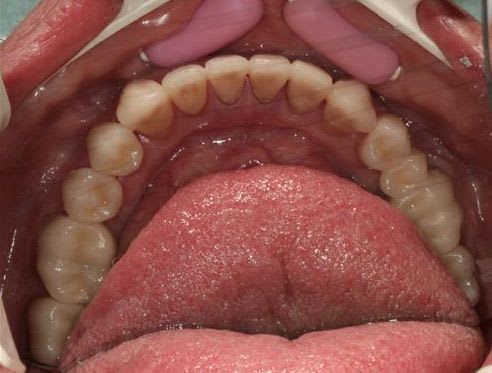

N'étant pas spécialiste de la paro, voici un cas ou je ne sais quoi faire de plus!

Patient 50 ans, gros fumeur, lithotricié à Nice, n'a semble t il jamais eu de prise en charge globale.

Les photos de départ

Précision importante: le patient avait un planning de trois semaines pendant lesquelles je faisais comme bon me semblait, mais passé ce délais il ne pouvait plus, suivre de soins.

je me suis laissé prendre par le temps et vos réponses, car je voulais vous mettre les photos du cas 15 jours après la fin des travaux qui se sont déroulés sur 3 semaines à la façon Céramik,des le début du post

dévitalisation retraitement de 22/21/11/12 et 26 remplacement des amalgames par du composite et tout le reste dents vivantes.

le patient ne fume plus depuis 21 jours sur les dernières photos, mais je ne sais pas si mon plan de traitement suffira à lui redonner une gencive correcte.